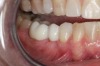

Fig 16. Final restorations (15 weeks postoperatively).

Figure 16

The final impression appointment follows the light-load phase, provided the implant is stable and the soft tissue is acceptable to the clinician. Polyvinyl putty and light-body impression materials were used in this case; analog casts and final full-zirconia full crowns were fabricated (Figure 16). The patient provided feedback that chewing was comfortable and without food impactions. Keratinized gingival cuff was developed, and natural-tooth contours for the restorations mimicked what is normally found in human dentition. The healed bone surrounding the ceramic dental implant was similar in density and crestal levels in comparison with the adjacent natural teeth, evident in the radiographic evaluation (Figure 17). Final long-term restorations at the gingival crest and restoration interfaces were also consistent in optimum periodontal health and gingival height. Arch-form integrity was upheld and occlusion was managed; osseointegration and light-load principles optimized the success of the restorations, and an acceptable, harmonious esthetic outcome was achieved for the patient.